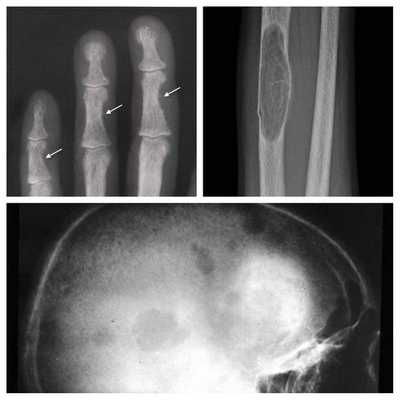

На рентгенограммах определяется остеосклероз, обызвествление реберных хрящей, по результатам денситометрии - повышенная плотность костей. МРТ выявляет отложение Ca во внутренних органах, подкожной клетчатке, ганглиях головного мозга. Для выявления скрытых форм гипопаратиреоза проводят пробы на определение повышенной судорожной готовности, пробу с гипервентиляцией.

Длительное течение заболевания сказывается на формировании костей. Так, н а поздних стадиях вовремя не диагностированного гиперпаратиреоза наблюдаются:

- разрушение дистальных или концевых фаланг конечностей;

- сужение дистального отдела ключиц;

- очаги разрушения костей черепа;

- бурые опухоли длинных костей.

Рентгенография позволяет обнаружить остеопороз, кистозные изменения костей, патологические переломы. Для оценки плотности костной ткани проводится денситометрия. При помощи рентгенологического исследования с контрастным веществом диагностируют возникающие при гиперпаратиреозе пептические язвы в желудочно-кишечном тракте. КТ почек и мочевыводящих путей выявляет камни. Рентгенотомография загрудинного пространства с пищеводным контрастированием бариевой взвесью позволяет выявить паратиреоаденому и ее местоположнение. Магнитно-резонансная томография по информативности превосходит КТ и УЗИ, визуализирует любую локализацию околощитовидных желез.